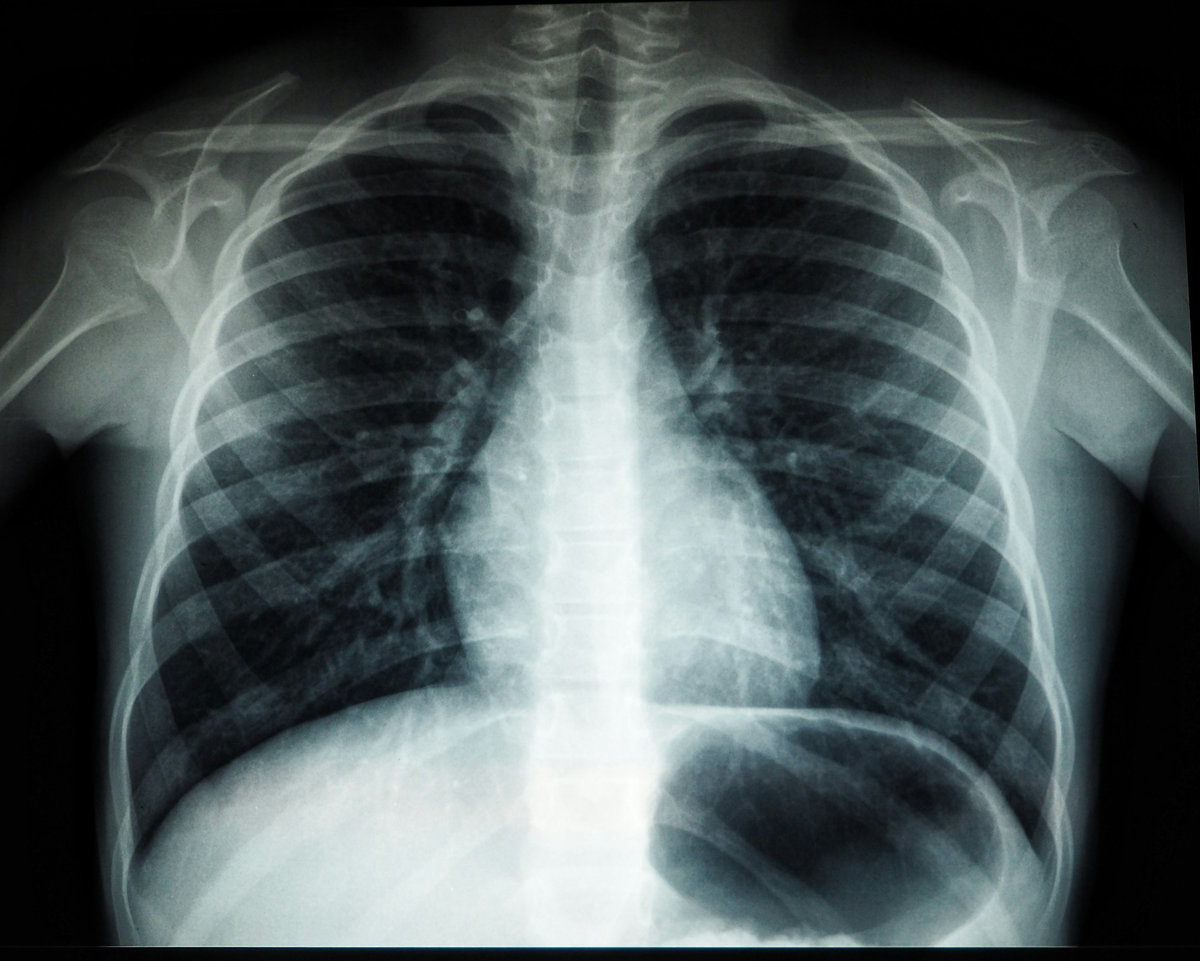

Diagnostika tuberkulózy je založená najmä na röntgenovom vyšetrení pľúc a laboratórnych testoch. Liečba je dlhodobá a trvá spravidla 6 až 9 mesiacov. Pozostáva z kombinácie viacerých liekov, pričom jej úspešnosť závisí najmä od dôsledného dodržiavania liečebného režimu pacientom. „Je nevyhnutné, aby pacienti užívali lieky počas celej stanovenej doby. Predčasné ukončenie liečby môže viesť k návratu ochorenia a jeho ďalšiemu šíreniu,“ zdôrazňuje.

Ilustračné foto, zdroj: Unsplash